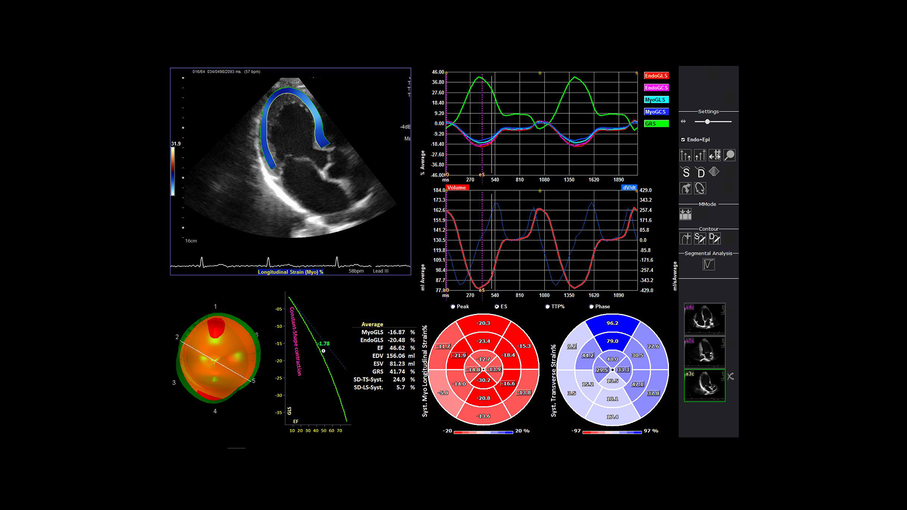

Кроме новой техники, можно заказать восстановленные медицинские системы: ультразвуковые сканеры, томографы, флюороскопы, ангиографы и хирургические установки С-дуга.